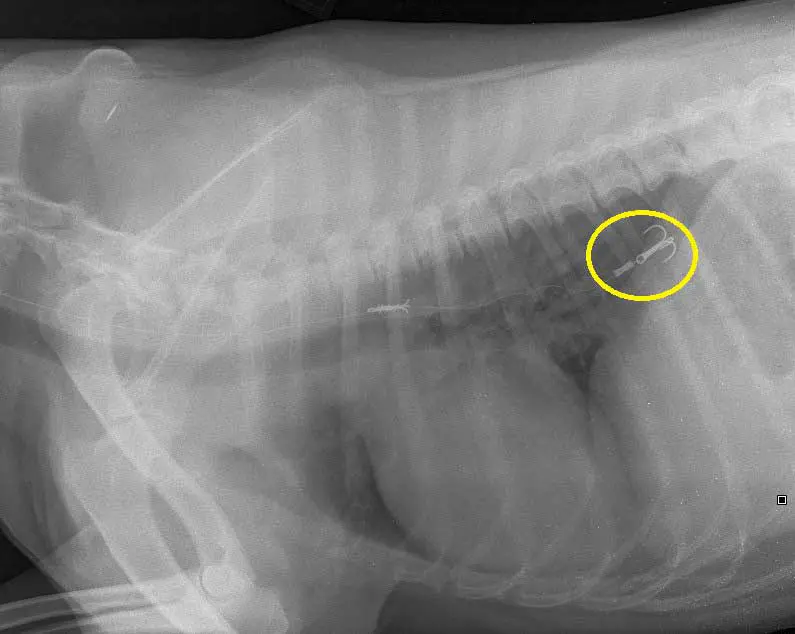

In the latest incident, a three-pronged hook was removed from three-year-old Chip, pictured, through endoscopy, which meant invasive surgery wasn’t required.

- Take cervical, thoracic and abdominal radiographs – hooks are usually clearly visible